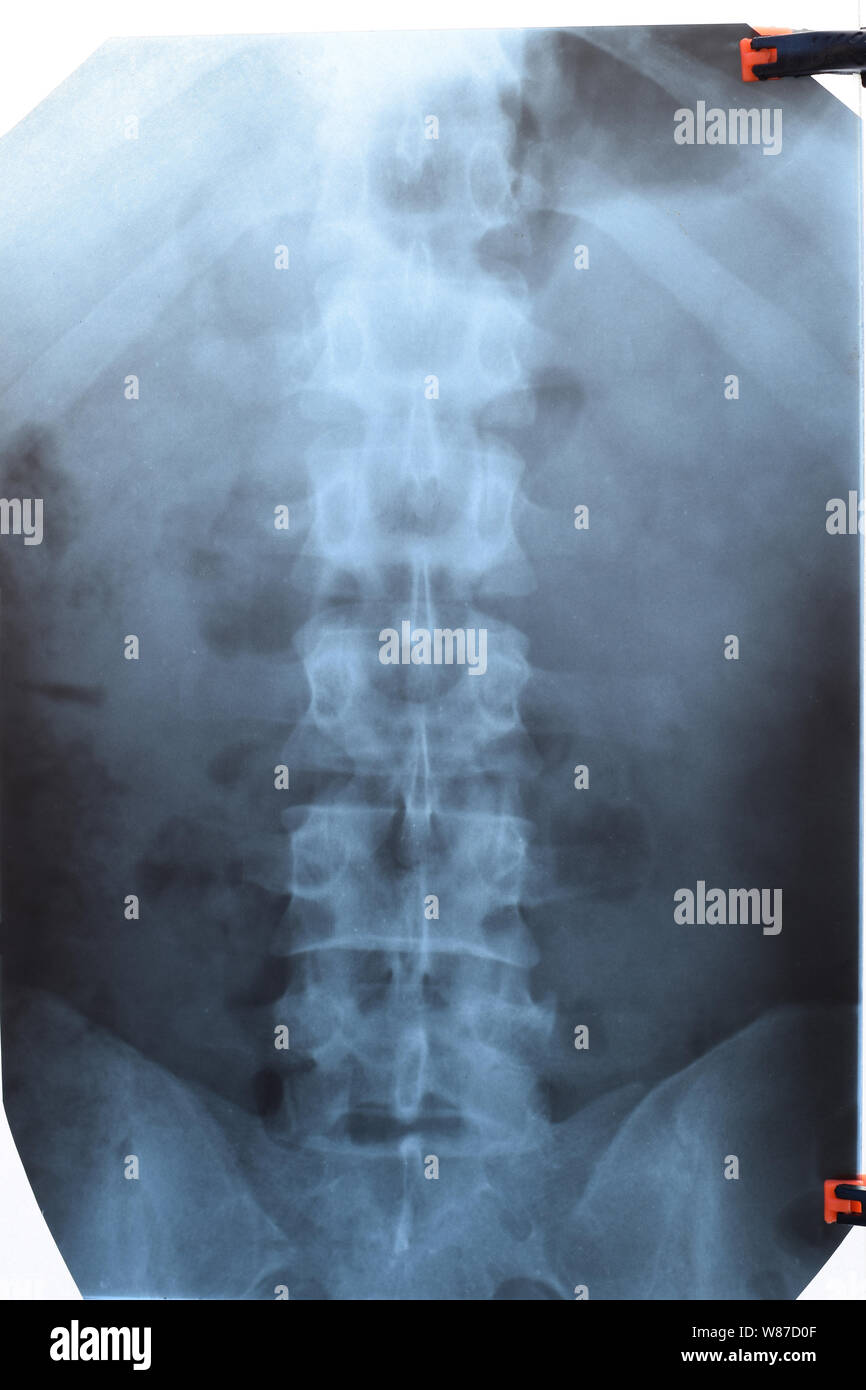

Lumbar Vertebrae Anatomy Xray How To Identify Vertebrae On X Ray Bony structures (vertebral body, uncus, transverse, spinous and. The vertebrae should be identified and counted slowly and bodies should be looked at from top to bottom. It should be checked that the alignment is in order and may be different depending on the. The entire lumbar spine should be visible, with a demonstration of t11/t12 superiorly and the sacrum inferiorly.. How To Identify Vertebrae On X Ray.